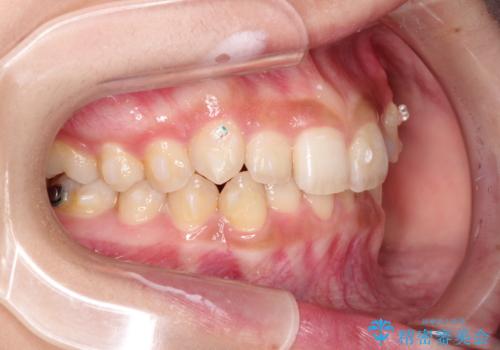

- 前歯のガタガタを主訴に来院された患者様です。

八重歯になっており、下顎の前歯が上顎の前歯に隠れてしまう、ディープバイトという状態でした。

インビザラインを使用して矯正する計画としました。